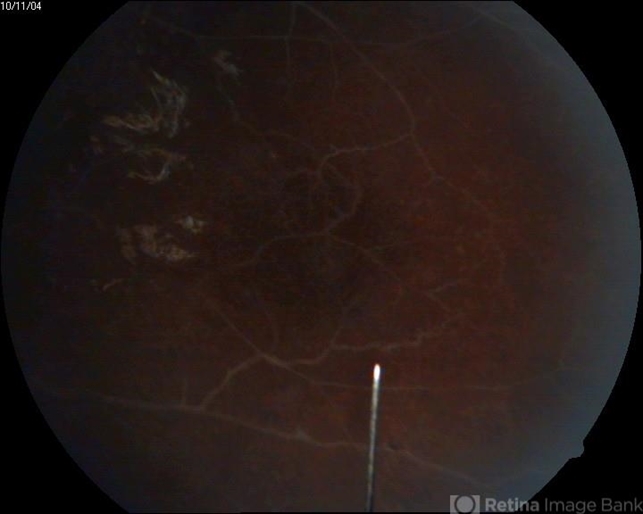

- Eales disease

- A 27-year-old male has been presented to us with sudden loss of vision OD and found to have vitreous hemorrhage, OS was found to have sclerotic vessels and perivasculitis.